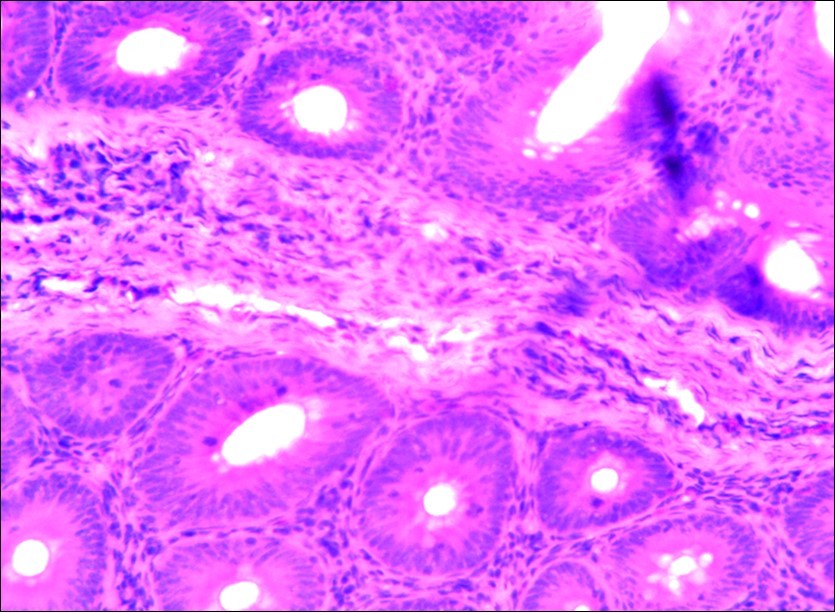

Figure 3.Photomicrograph of caecum of chick uninfected and untreated showing no observable lesion X250 (H&E).

In this study, the reduction in oocyst count observed in the treated group was compared with amprolium could be attributed to the presence of a bioactive compounds azadiractin A which is known to bind membrane cholesterol, altering the integrity of the parasite membrane, resulting in loss of homeostasis and eventual death of the parasite 29]. Also, limonoids contained in NeemAzal® inhibit protein digestion and uptake of vitamins and minerals by the parasites in the gut 17. This action results in impaired nutrient utilization, reduced growth, and multiplication of the parasite which could contribute to the reduced oocyst count observed. Extracts of neem and mahogany when used individually have been reported to reduce oocyst count in avian coccidiosis 11,12. The observed reduction in oocyst count and the significant increase in weight gain of the birds when treated with NeemAzal®, as compared with the negative control group could probably be due to the inhibition of inflammation in the intestinal mucosa which is suggestive of an increased nutrient absorption across the intestinal wall and enhanced feed conversion ratio compared to the negative control this is in agreement with reports by Nwosu et al.12 and Biu et al.11 who also reported an increased weight gain and feed conversion ratio in birds treated with only Khaya senegalensis extracts and Azardiractaindica, respectively. The observed increase in RBC and haemoglobin concentration is indicative of the erythropoieticability of the NeemAzal®, which is beneficial since the Eimeria parasite in the epithelia of the intestines causes bloody diarrhoea and consequently anaemia (Table 1). This finding is in consonance with 15 who reported an anti-anaemic effect of Khaya Senegalensis on phenyl hydrazine-induced anaemia in rats. Neem has been shown to possess anti-anaemic properties in rats 14. The significant increase in mean weight gain in treated birds when compared to the negative control is possibly due to the inhibition of inflammation in the intestinal mucosa which is suggestive of an increased nutrient absorption across the intestinal wall and enhanced feed conversion ratio compared to the negative control. Nwosu et al.12 and Biu et al.11 reported an increased weight gain and feed conversion ratio in birds treated with only Khaya Senegalensis andAzadiractaindica extracts, respectively. In a similar study, Neem acts like toltrazuril exhibiting anticoccidial. In addition, exposure of broiler chickens to 20000 Oocysts of Eimeria tenellacaused generalized degeneration of the caecal glands with massive Oocysts and gametocyts within the caecal glands with fibrosis (Figure 3, Figure 4 & Figure 5), however, broiler chickens treated with NeemAzal® post exposure to 20000 Oocysts of Eimeria tenella, shows equal numbers of caecal tissues with non-observable histopathological lesions (Figure 4), possibly due to the antioxidant and anti-coccidian effects of NeemAzal®. The exact mechanism of action of neem against coccidian parasites is unknown, but a report by the National Research Council 1992 30, suggested that aqueous neem leaf extract, when taken orally, produces an increase in red cells, white blood cells and lymphocyte counts thus enhancing the cellular immune response, increasing antibody production and so most pathogens can be removed before they cause the symptoms associated with disease this was in agreement with this study as seen in Table a remarkable increase of the RBCs.

In addition, the generalized degeneration of the caecal glands, moderate numbers of gametocytes within the glandular regions with fibrosis which underscores reparative process in response to injury evoked by coccidiosis in the chicks which was perhaps brought about by the antioxidant and chemotherapeutic effect of NeemAzal®. The observed increase in RBC and hemoglobin concentration (Table 1) is indicative of the erythropoieticability of NeemAzal®, which is beneficial since the Eimeria parasite in the epithelia of the intestines causes bloody diarrhea and consequently anaemia. This finding is in consonance with 15 who reported an anti-anaemic effect of Khaya senegalensis on phenyl hydrazine-induced anaemia in rats. If the results of this study are juxtaposed with the results of the previous studies on potent antioxidant, hepatoprotective and mitigative role of methanolic extracts of Azadirachtaindica,in both natural and experimental infection with Eimeria species and can be deduced that, NeemAzal® could be said to be a potent antioxidant, chemotherapeutic and tissue protective agent. This study also answered a question on further study advocated to determine the maximum safe levels of neem supplementation because the higher doses, due to its bitterness, may show adverse effects on feed intake which will change the performance parameters of birds (Figure 6 and Figure 7) . Light microscopic inspection of hematoxylin and eosin-stained sections revealed that the epithelial cells of the Cecum were infected by E. tenella(Figure 3 and Figure 4). The results of the safety study showed that exposure of chickens to NeemAzal® at 200mg/kg body weight did not alter the histoarchitecture of liver and kidney (Figure 6 & Figure 7) which is similar to the work conducted in the same environment by a group of Scientists 34. It is therefore recommended that NeemAzal® could be used as a coccidiostat to replace the expensive anti-coccidiostats in the market.